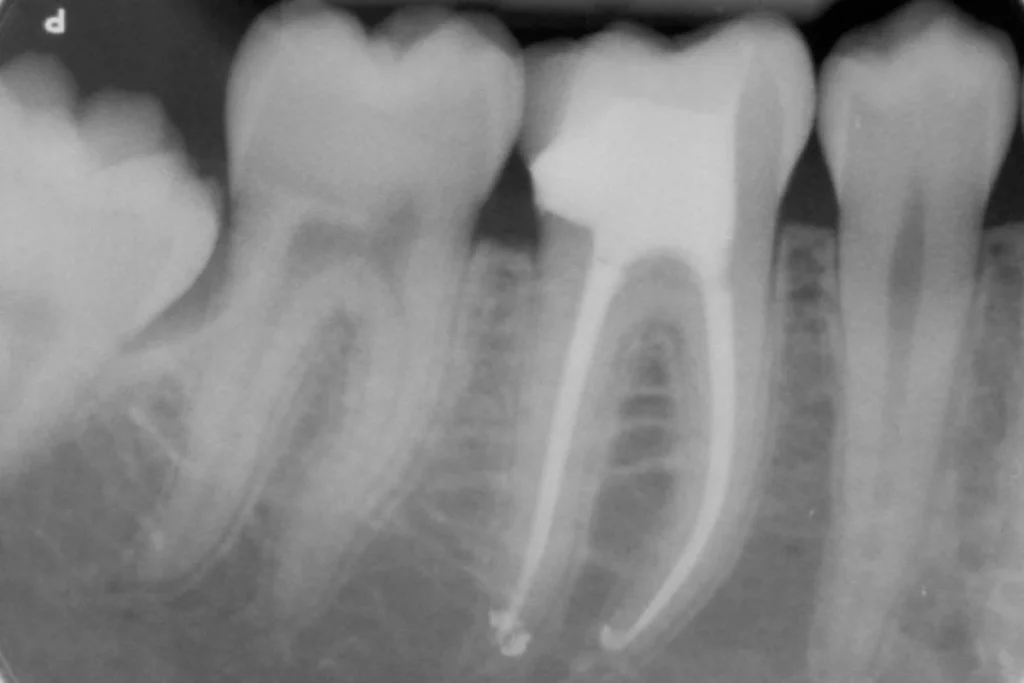

Restauration d’une dent dévitalisée avec un inlay / onlay en céramique